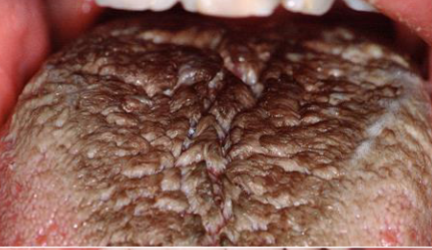

hairy tongue

excess keratin on surface of filiform papillae